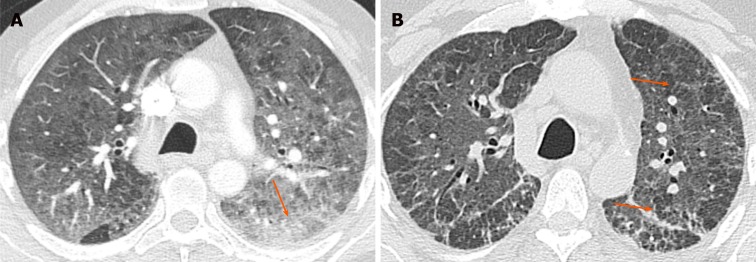

The typical imaging finding is presence of middle/upper and peripheral lung predominant chronic airspace opacity and consolidations[9]. The opacities may persist over time but usually show subtle or major changes in appearance and therefore are migratory (Figure 2). Crazy-paving with GGO and interlobular septal thickening have also been described[7].

Figure 2.

Chronic eosinophilic pneumonia. A: Baseline non-contrast chest computed tomography in a 38-year-old woman with history of asthma, eosinophilia and eosinophilic pneumonia, who presented with shortness of breath, showed bilateral patchy airspace opacities in both upper lobes (arrows); B: Follow-up chest computed tomography after 8 mo showed resolution of the previous opacities with interval development of an area of patchy consolidation in the left upper lobe (arrow).

The diagnosis is based on respiratory symptoms, alveolar and/or blood eosinophilia, airspace opacifications, and exclusion of other causes of eosinophilic lung disease[10]. Overall, chronic eosinophilic pneumonia carries a good prognosis. However, it often needs long-term low-dose corticosteroid treatment in order to prevent relapse[10].